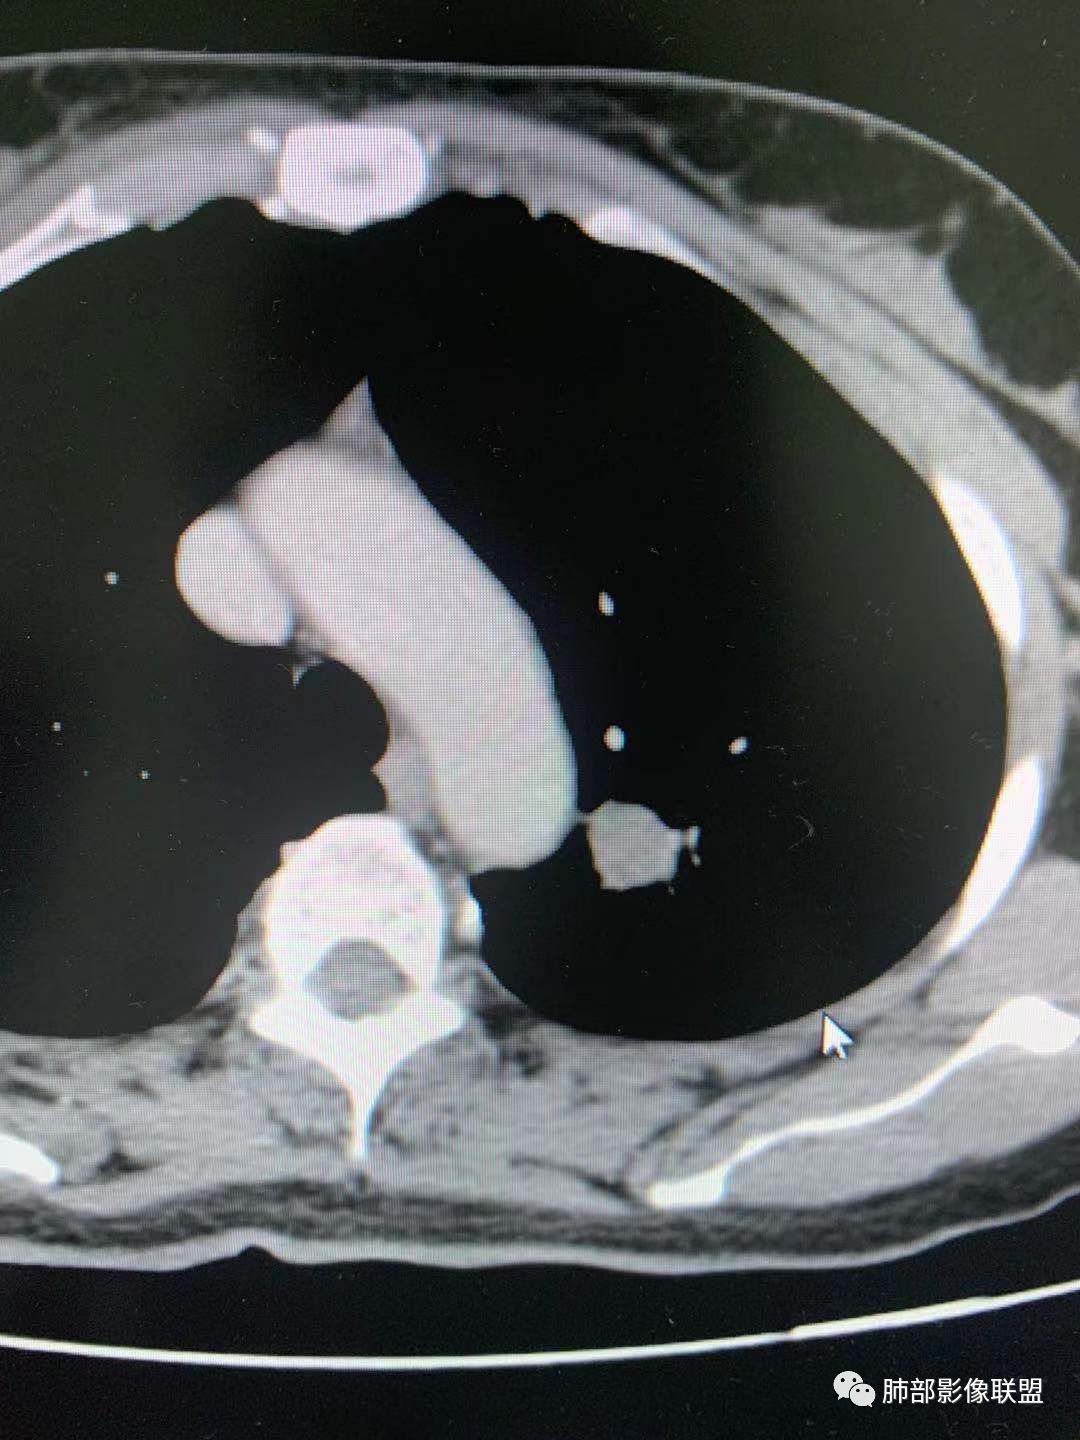

左肺上叶实性结节,光滑,支气管血管贴边,晕,强化持续。两年前就有,考虑psp。另外左肺上叶纵膈侧胸膜下及中带两处混合磨玻璃结节,考虑原位和微浸润可能,需要随访看看。

左肺上叶实性结节,边缘光滑清晰,血管贴边,渐进性延迟强化,密度均匀,考虑PSP. 医学百科网 | YxBaike.Com

贴边血管征,强化延迟,考虑PSP 医学百科网 | YxBaike.Com

左肺上叶实性结节,边缘光滑清晰,血管贴边,渐进性延迟强化,密度均匀,考虑PSP.但是强化幅度不够,需要鉴别早期肺癌

最大的靠后,有血管贴边征,渐进性明显强化,考虑PSP可能大

中年女性,左肺上叶实性圆形结节,边缘有晕,血管及支气管贴边,强化尚均匀,渐进性明显强化,考虑为PSP可能 医学百科网 | YxBaike.Com